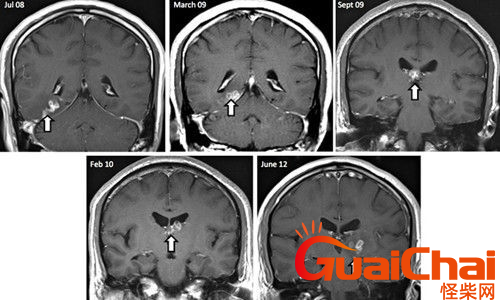

专家介绍,黄女士患的是脑囊虫病,这是由寄生虫(猪肉绦虫为主)所传染的一种顽固性颅脑内疾病,不排除与她平时喜欢吃烧烤有关,如果不慎吃下被猪肉绦虫寄生且没烹饪熟的“米猪肉”后,猪肉绦虫虫卵在人体内发育成囊尾蚴,经消化道穿出肠壁进入肠系膜小静脉,再经体循环到达脑膜、脑实质及脑室内。患者患上此病,会致脑组织及大脑中枢损伤严重,头疼、浑身无力、肢体运动障碍,最严重的是继发癫痫,视物不清,甚至失明等。

今年6月份,张敏在宿舍休息时,又发起了癫痫,也是口吐白沫,浑身抽搐。送到苏州一家大医院,头颅核磁共振检查出,张敏大脑右额叶处有一处病灶,也就是大脑额头处有个东西。

脑袋里的东西,到底是肿瘤还是其他什么东西,这个谜像个石头一样,压得张敏一家人喘不过气。7月份,张敏一家又来到南京脑科医院求医,第三次检查后,医生觉得很像是寄生虫。不过,影像的检查,只能作为医生推测的依据,具体是什么,只有手术拿出来后才能知道。